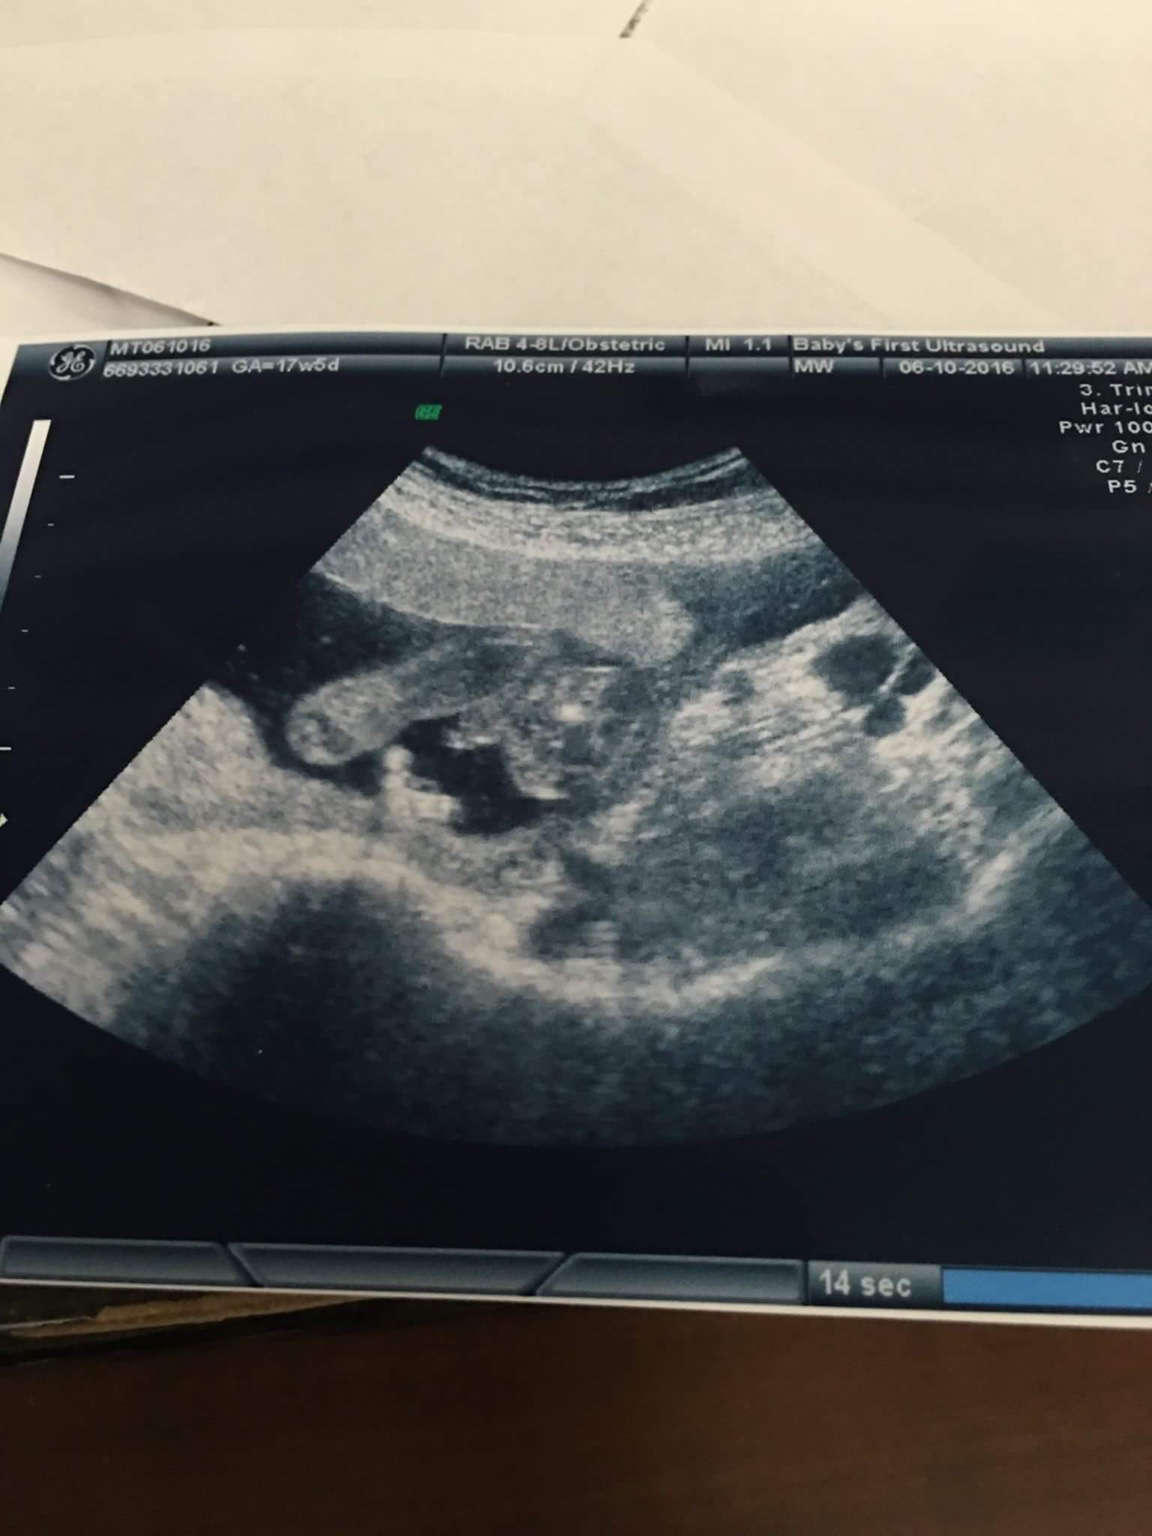

looks girly to me :)

Looks girly with maybe a bit of cord down there.

I think girl

What would mine be?Attachment 31813Attachment 31814